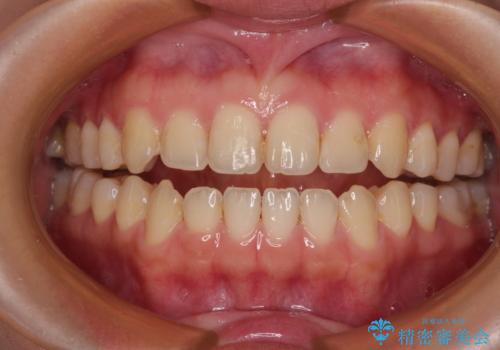

ウェディング前のホワイトニングとエアーフロー

担当医 歯科衛生士